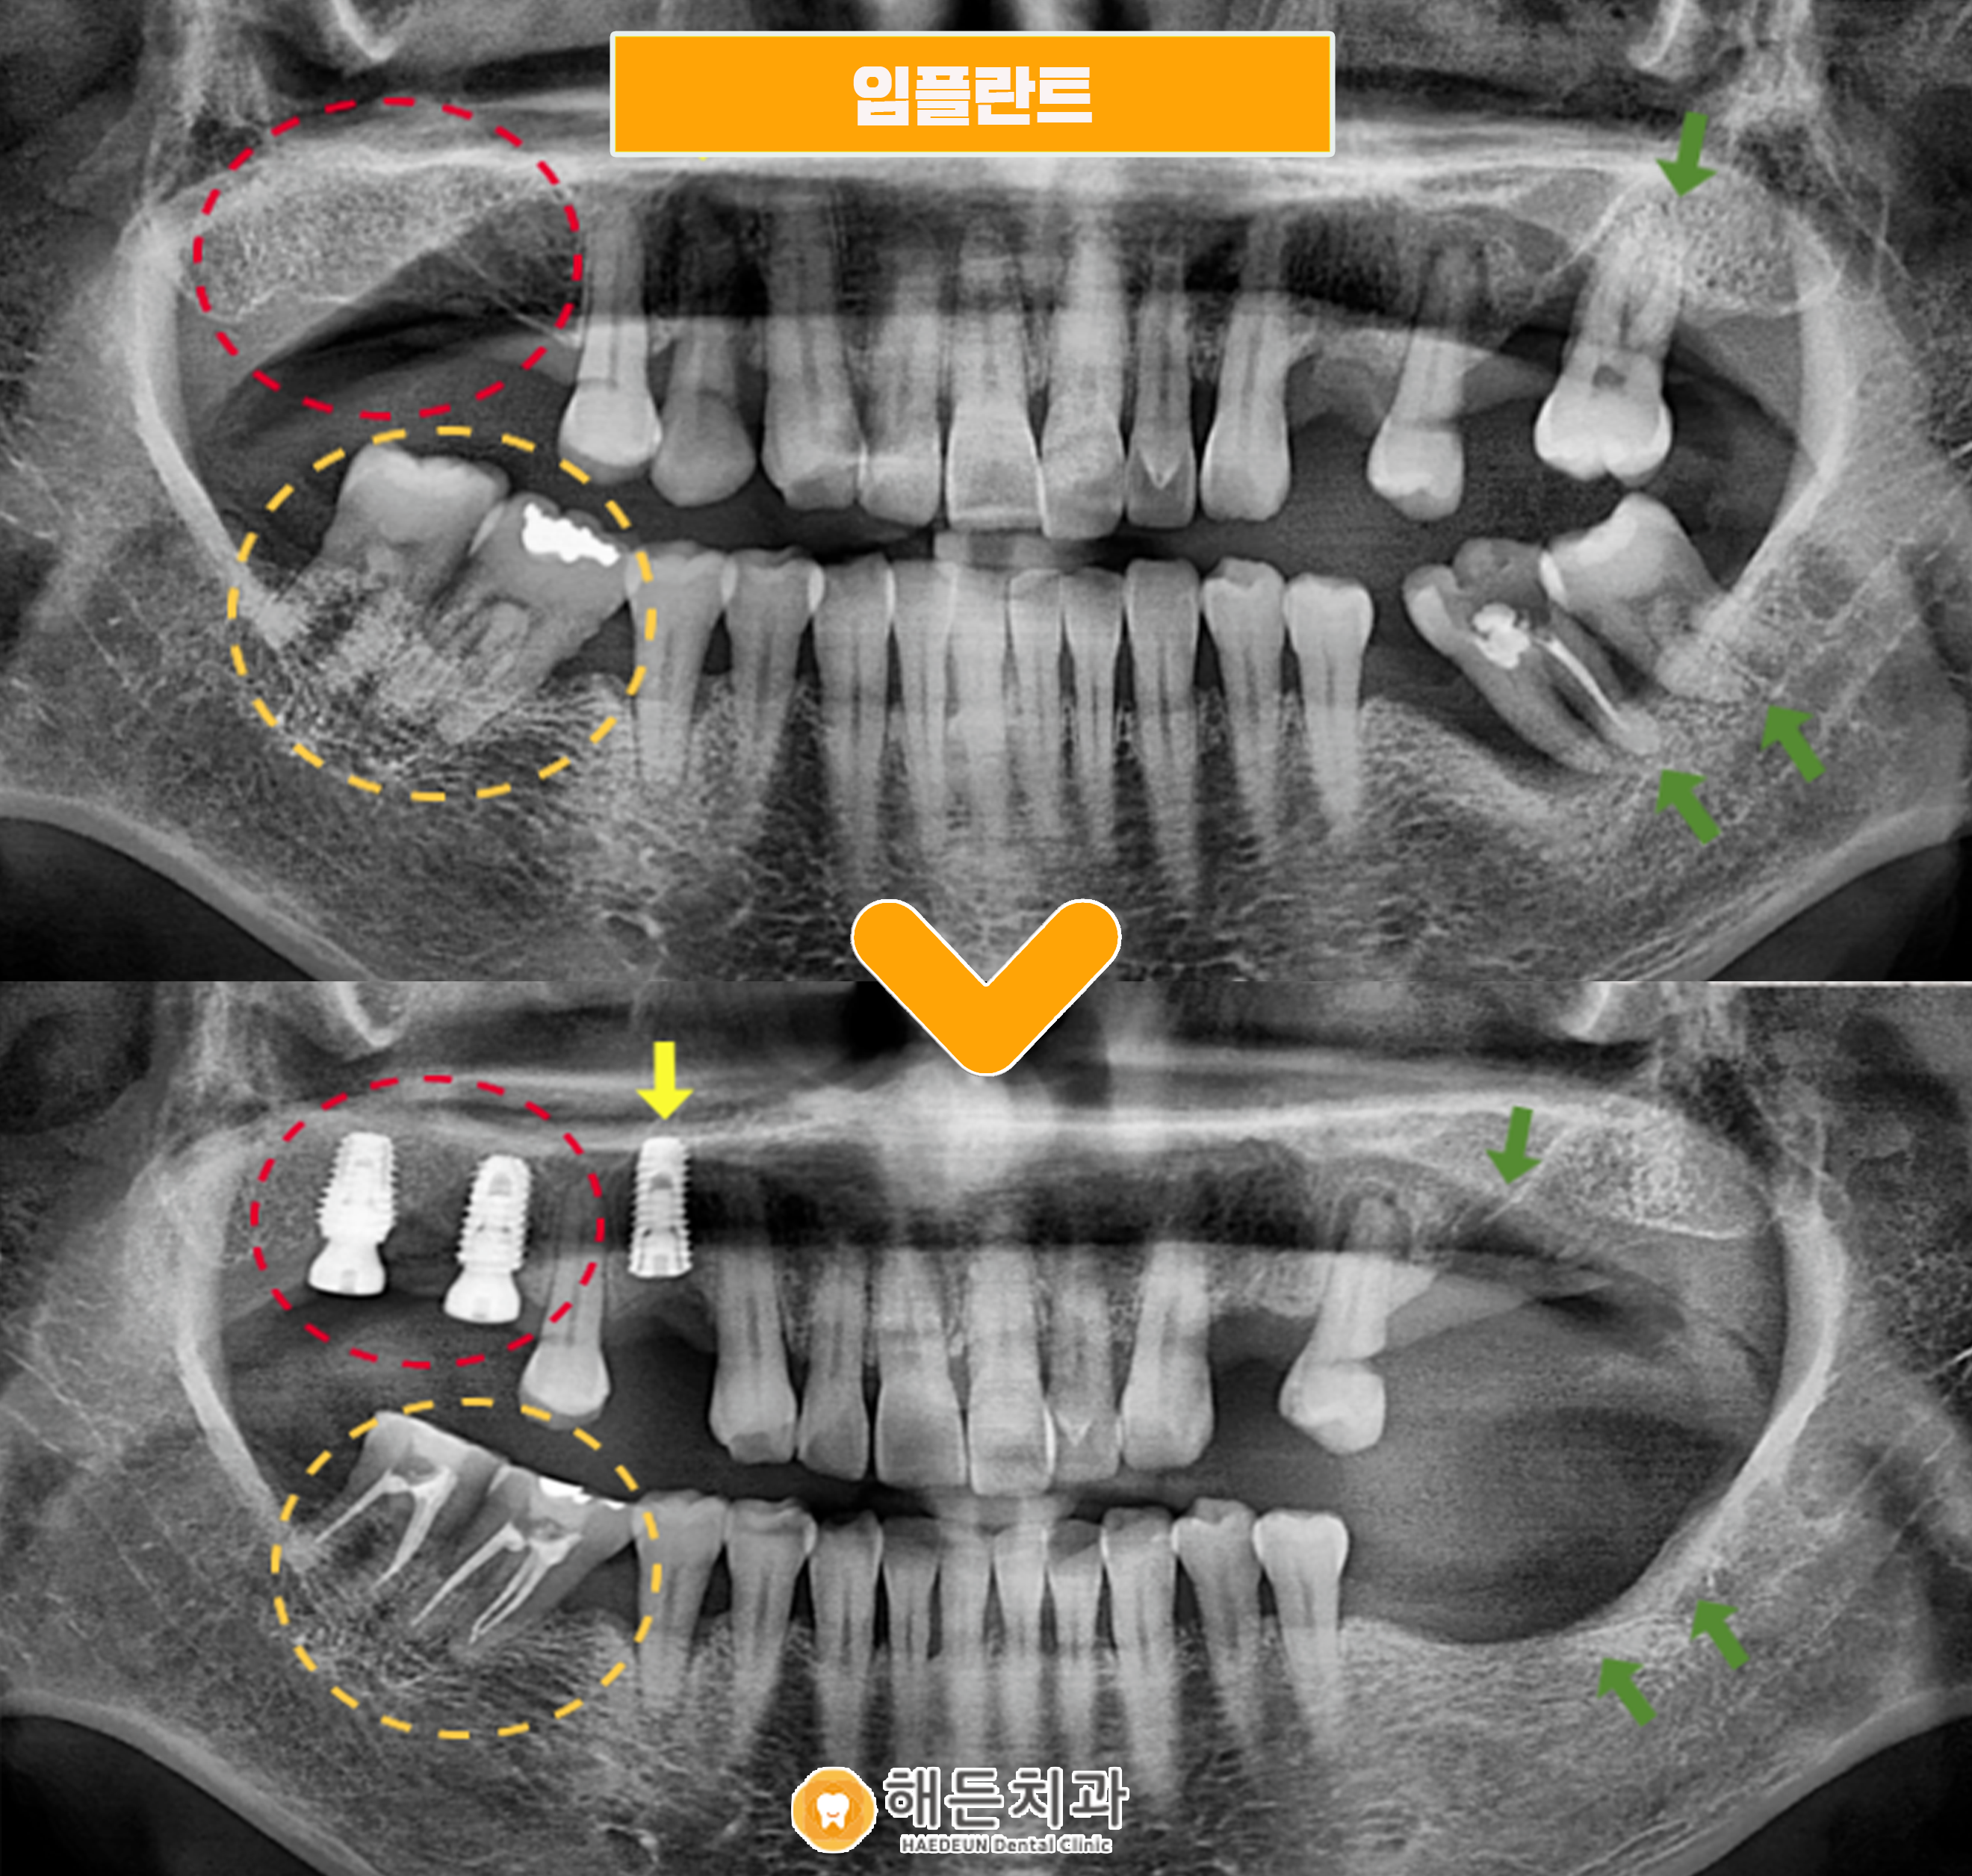

오늘 소개해 드릴 분께서는 빨간색 동그라미 표시의, 오른쪽 위턱 어금니 부위의 임플란트 치료를 원하셨는데요. 치주 질환으로 인해 잇몸 건강이 나빠지면서 어금니 치아를 상실하게 되었다고 말씀해 주셨습니다.

파노라마사진을 촬영하여 검사해 보았더니, 환자분께서 치료를 원하시는 부위를 제외하고도 문제가 있는 치아들을 다수 확인할 수 있었는데요.

✔ 노란색 화살표의 오른쪽 위턱 첫 번째 작은 어금니(#14) 주변으로 잇몸뼈가 많이 녹아 동요도가 심하여, 발치가 필요한 상황이었습니다.

✔ 그리고 주황색 동그라미의 오른쪽 아래턱 어금니 부위에는 첫 번째 큰 어금니(#46)가 상실한 상태라, 나머지 두 어금니(#47,48)가 첫 번째 큰어금니 자리로 많이 기울어져 있었으며 위에 맞물리는 어금니가 없다 보니 위로 솟구쳐 올라와 있었습니다.

✔ 또한 왼쪽 위아래 어금니 부위도 주변 치아 상실로 인해 치아가 많이 기울어져 있었으며 주변 잇몸 상태도 많이 안 좋아 동요도가 있는 상황으로, 발치가 필요한 상태였습니다.

오른쪽 위턱 첫 번째 작은 어금니(#14)는 발치 후 임플란트, 기존에 상실되어 있던 큰 어금니(#16,17) 부위에는 임플란트를 식립하기로 하였고,

아래턱 두 번째 큰 어금니(#47)와 사랑니(#48)은 위아래 교합을 맞추기 위해서 신경치료 후 크라운 수복을 하기로 하였습니다.

그리고 동요도가 심한 왼쪽 위아래 큰 어금니는 우선 발치까지만 진행하기로 하였고, 오른쪽 치료가 끝나고 식사가 편안해지면 그 때 임플란트를 진행하시기로 치료 계획을 수립하였습니다.

오른쪽 위턱 첫 번째 작은 어금니(#14)는 발치 후 주변 염증을 깨끗하게 제거한 뒤 잇몸뼈가 어느 정도 차오를 때까지 기다린 후에 임플란트 식립을 도와드렸으며, 큰 어금니 (#16,17) 부위는 잇몸뼈의 양과 주변 컨디션이 좋아 바로 식립을 도와드렸습니다.

위턱 어금니(#16,17) 임플란트 보철물이 올라가는 작업이 진행되기 전까지 맞물리는 아래턱 어금니(#47,48) 부위의 신경치료를 깨끗하고 깔끔하게 도와드린 뒤 차후 위아래 교합을 맞춰 같이 보철물이 올라갈 예정입니다.

왼쪽 위아래 어금니 부위도 발치 후 잇몸뼈가 어느 정도 차고 아문 모습을 확인할 수 있는데요. 오른쪽 치료 마무리 후 왼쪽 치료 계획 상담을 도와드릴 예정입니다. ^^

🦷 전 >후 🦷